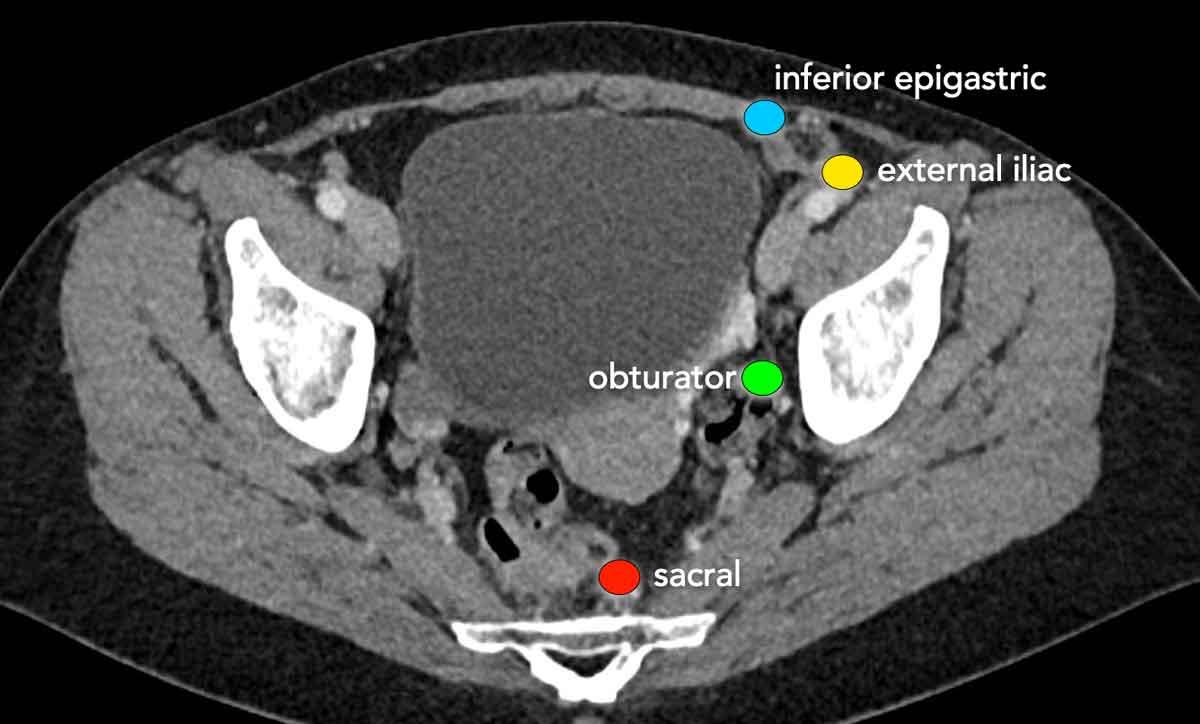

Phân giai đoạn hạch bạch huyết

Các hạch bạch huyết vùng trong phân giai đoạn ung thư cổ tử cung bao gồm tất cả các hạch trong vùng chậu và các hạch cạnh động mạch chủ đến ngang mức tĩnh mạch thận.

Việc phát hiện di căn hạch cạnh động mạch chủ rất quan trọng, vì sự hiện diện của các hạch này đòi hỏi phải điều chỉnh trường xạ trị.

Hạch bạch huyết bẹn và hạch cạnh động mạch chủ trên mức tĩnh mạch thận được coi là di căn xa.

MRI có hiệu năng chẩn đoán hạn chế trong phân giai đoạn hạch bạch huyết vùng chậu.

Phương pháp này chủ yếu dựa vào kích thước hạch như một tiêu chí; ngưỡng kích thước thay đổi trong y văn nhưng ngưỡng thường được sử dụng là 1 cm.

Độ nhạy (±40-90%) và độ đặc hiệu (±80-100%) được báo cáo của MRI dao động rộng.

PET/CT chính xác hơn MRI và được sử dụng để phân giai đoạn hạch bạch huyết vùng chậu, cũng như để đánh giá hạch cạnh động mạch chủ và di căn hạch xa trên mức tĩnh mạch thận (3).